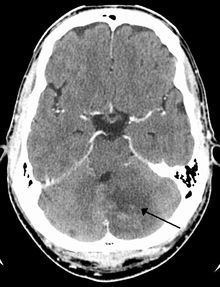

Cerebellar stroke syndrome is a condition in which the circulation to the cerebellum is impaired due to a lesion of the superior cerebellar artery, anterior inferior cerebellar artery or the posterior inferior cerebellar artery.[1]

Cerebellar strokes account for only 2-3% of the 600 000 strokes that occur each year in the United States.[3] They are far less common than strokes which occur in the cerebral hemispheres. In recent years mortality rates have decreased due to advancements in health care which include earlier diagnosis through MRI and CT scanning.[4] Advancements have also been made which allow earlier management for common complications of cerebellar stroke such as brainstem compression and hydrocephalus.[4]